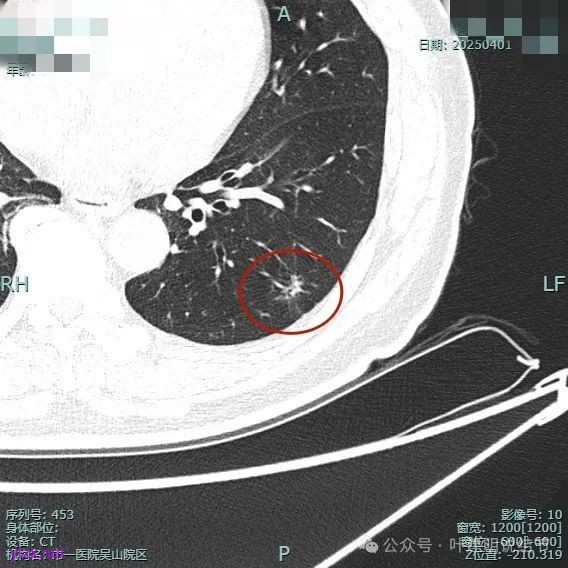

再看2025年4月初复查的情况:

整体纵向仍偏长条些,实性部分不太致密,边上磨玻璃成分的轮廓与界限不太清楚,毛刺显得长。

仍有支气管扩张,但较2024年时密度感觉低了点。

密度较淡且缺乏收缩力。

密度杂乱,血管进入,但血管说不上明显异常增粗,磨玻璃成分淡而瘤肺界限欠清。

总体较之前密度有减低,缺乏聚拢性。